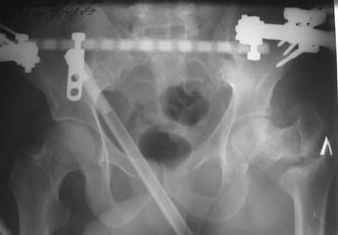

Возможно, пример (в приложении) поможет Вам определиться с выбором тактики лечения (у нашего пациента, кроме тугого ложного сустава вертельной области, сложная деформация н/3 бедренной кости; т.к. это не имеет значения к обсуждаемой теме - оставил "за кадром"). Как Вы видите, мы в данном случае не вводили чрескостные элементы в зону установки имплантата. При отказе от наложения опоры на таз (кстати, она не обязательно может быть громоздкая спицевая; арки со стержнями-шурупами, введенными в крыло подвздошной вполне достаточно) "не удивляйтесь", если опора со стержнями-шурупами, введенными в вертельной области в скором времени дестабилизируется, возникнет воспаление мягких тканей у чрескостных элементов. Такая опора "имеет на это право": нагрузка конечности от вершины дистального фрагмента до кончиков пальцев ляжет на нее. А двух-трех введенных рядом стержней-шурупов, как их не разноси от фронтальной плоскости, в данном

случае явно недостаточно для адекватной фиксации. + для того, чтобы выбрать оптимальные чрескостные элементы для промежуточной и дистальной опор, можете воспользоваться атласом